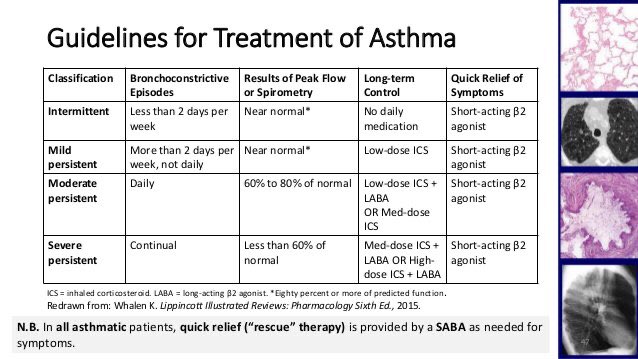

🔴خامسا :classfication of asthma ؟

#ملاحظه :

هذا السؤال مرره مهم عشان نكتب الخطه

التصنيف نعرفه بثلاث اشياء /

اولا: نشوف الاعراض

ثانيا: نشوف FEV الي هو/

Forced Expiratory Volume

وهو لازم يكون 95%

ثالثا : nighting awakening

وراح اشرحهم بالتفصيل تحت لا تخافو من الصورة 👇

First : #intermittent patient:

1- if symptom >2 days per week but not daily

2- FEV 1 80% , FEV / FVC > 80 %

ويكون النسبة اقل من 80%

3_nighting awakening: 3 or 4 times monthly

ويصحو بالشهر 3 او اربع مرات

اما الاطفال مرره او مرتين يصحوا من النوم بالشهر من تعب الربو

First : #Mild patient:

1- if symptom >2 days per week but not daily

2- FEV 1 80% , FEV / FVC > 80 %

3_nighting awakening:5 to 6 times per month

اما الاطفال 3 او 4 مرات يصحوا من النوم بالشهر

Second : #Moderate patient:

1- if Symptom Daily

2- FEV1 (60 - 80) % , FEV / FVC (75-80)%

يعني نشوف الFEV اذا من 60الى 80 هذا Moderate

3_nighting awakening: more than once weakly

اما الاطفال 4 الى 5مرات يصحوا من النوم

4_ #Sever patient:

المريض الشديد

1- if Symptom Throughout the day

2- FEV1 < 60 % predicted , FEV / FVC <75 %

اقل من 60% 😔

3-Nightly awakening: more than 5 times or daily

اما الاطفال اكثر من مره يصحوا من النوم بالاسبوع

🔴ثامنًا: ايش هي الخطه العلاجيه بالترتيب :

بعد مايرد طبيعي تبدأ الخطه كالتالي

وهنا دايما خطة الchronic تبدأ

يلا نبدأ خطة المزمن #chronic /

if symptom less than 2 days per week Will be #intermittent(before mild) & Give him: #step 1

#Step 1: SABA (short acting beta agonist )PRN

يعني احد ادوية SABA يعني عند اللزوم